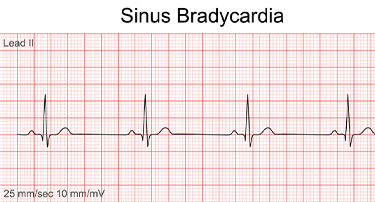

Bradycardia: Causes, Symptoms And Treatment Of Low Heart Rate

Bradycardia, also known as a low heart rate or slow pulse, is a condition where the heart beats fewer than 60 times per minute. While a slow heart rate can be a normal occurrence for some, such as athletes or people in excellent physical condition, it can also be a sign of an underlying health issue.